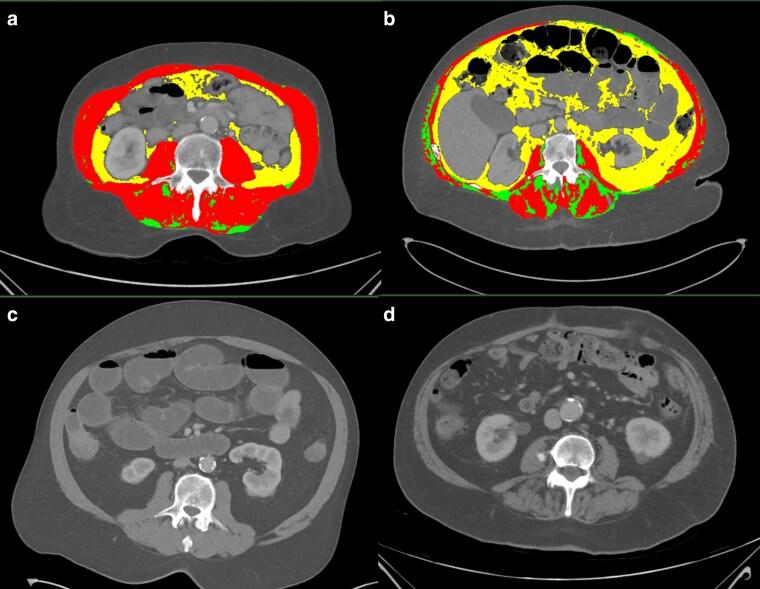

Patients aged greater than or equal to 55 years who underwent emergency laparotomy and preoperative computed tomography (CT) at two hospitals in New Zealand between February 2022 and October 2023 were included in a prospective database. Sarcopenia was measured using the SARC-F questionnaire, isokinetic dynamometry to measure hand grip strength, and skeletal muscle quantity according to CT. Myosteatosis was determined using CT and frailty was assessed using the Clinical Frailty Scale. Predictors for rehabilitation, days alive and out of hospital at 90 days, and risk of not returning home were analysed using relative risk and proportional means regression. Secondary outcomes were 3- and 6-month mortality and inpatient morbidity defined using the Clavien-Dindo classification.